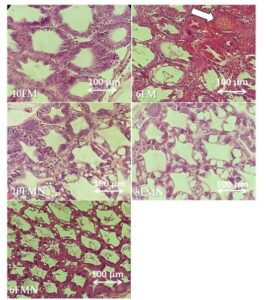

Tóm tắt Giới thiệu Vi bào tử trùng Enterocytozoon hepatopenaei lần đầu được phát hiện...